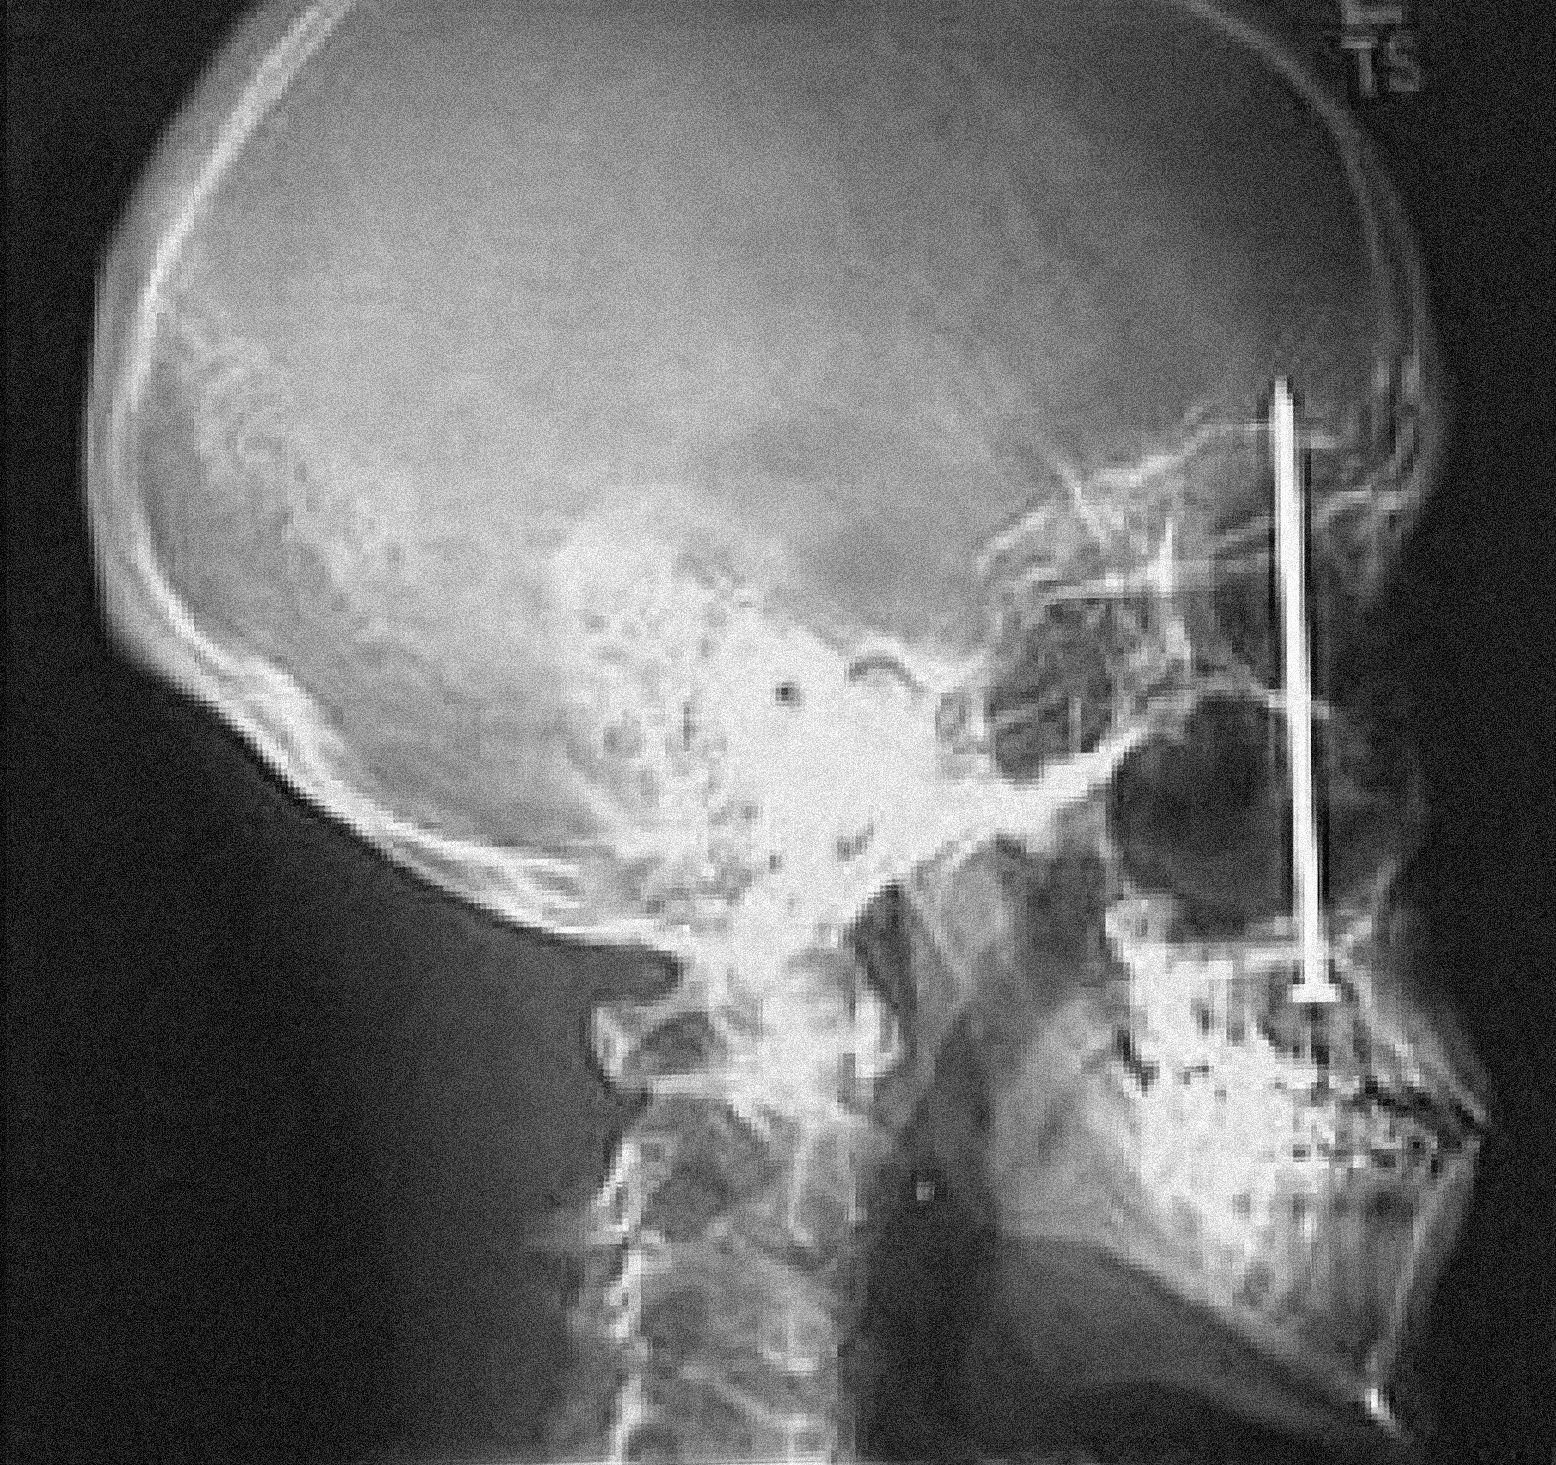

С другой стороны, многие из нас знакомы с получением травм, иногда серьезных, которые не болят в начале — боль появляется позже, если вообще появляется, и иногда кажется, что она зависит от нашего более высокого уровня осознания травмы. Приведу один жуткий пример: в начале 2005 года строитель в Колорадо испытал то, что он воспринял как болезненный удар от рикошетящей гвоздезабивной машины на строительной площадке. Шесть дней спустя он посетил стоматолога, жалуясь на легкую зубную боль; он прикладывал лед и принимал «Адвил». Рентгеновский снимок показал, что он выстрелил четырехдюймовым гвоздем через небо рта и в свой мозг. Он хорошо восстановился после операции по удалению гвоздя, но эта газетная история не вдохновляет меня заниматься более сложными делами по дому.

Рентгеновский снимок четырехдюймового гвоздя, вонзившегося в череп двадцатитрехлетнего строителя Патрика Лоулера, удаленного в больнице Литлтона в Денвере 14 января 2005 года, через шесть дней после того, как Лоулер неосознанно выстрелил в себя из гвоздезабивной машины.